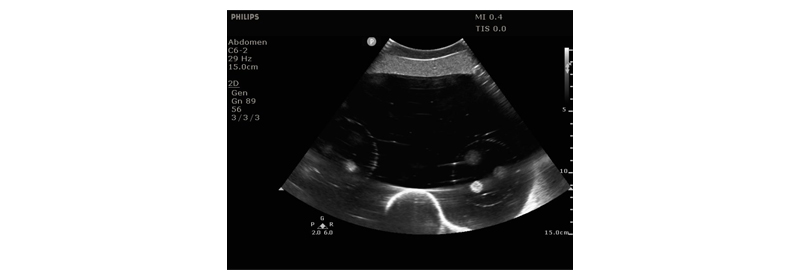

Cirs 071B圖像引導(dǎo)腹部穿刺模體,Cirs 071B腹部模體是一種簡(jiǎn)化的腹部模型,適用于訓(xùn)練和演示圖像引導(dǎo)的穿刺活檢導(dǎo)航工具或程序,需要持續(xù)的視覺(jué)參考針頭放置。因?yàn)樗怯蒢erdine的自我修復(fù)配方構(gòu)成,所以體模允許多次活檢插入,并且針跡追蹤最少。Cirs 071B圖像引導(dǎo)腹部穿刺模體,Cirs 071B腹部模體包含12個(gè)病灶,直徑5-12mm,在體模內(nèi)的一致位置以三個(gè)一組的方式定位。它還包括模擬脊柱和肋骨,以及脊柱內(nèi)的“H”標(biāo)記,以幫助確定CT圖像中的頭側(cè)。

適用于CT和超聲波